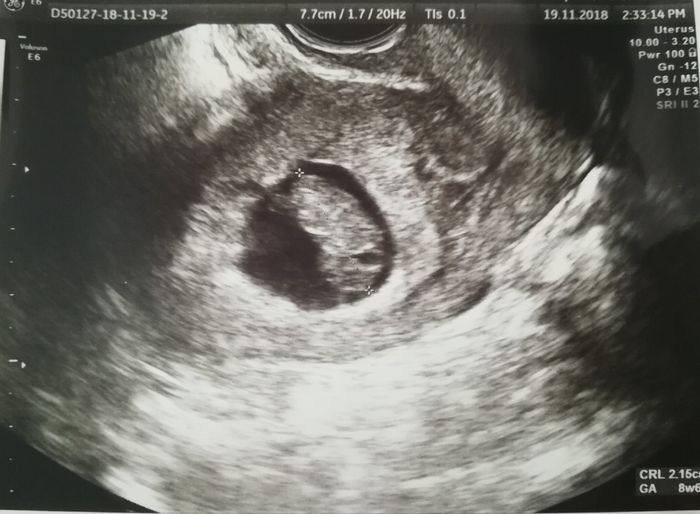

Ho caricato una foto nel post di Stella

Ciao ragazze!! Venerdì mattina finalmente ho avuto la mia prima ecografia! Dovrei essere di 8 settimane ma mi ha ridatata a 7+1 poi mi ha detto che tra un mese, alla translucenza mi ridaterà con più precisione... Il mio fagiolino misura 8 millimetri...